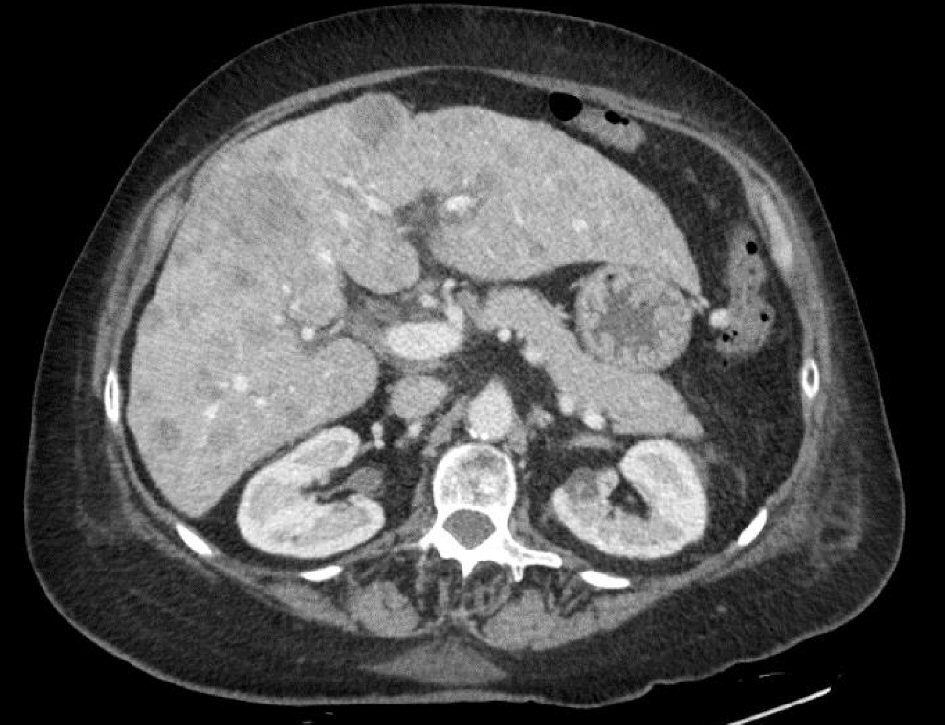

Upon arrival, her vitals were stable. On physical exam, she had moist oral mucosa without pharyngeal erythema. Her uvula was enlarged but not obstructing the pharynx. She had no palpable cervical lymph nodes. Chest examination revealed limited air entry with mild expiratory wheezes with coarse breathing sounds. Heart sounds were regular without murmur. She had 1+ lower extremity edema. Complete blood count (CBC) showed white blood cells of 11.7 × 103/µL, hemoglobin level 14.3 mg/dL, platelet count of 123 × 103/µL. INR was 1.2. Serum procalcitonin level was 171.37 ng/mL. Comprehensive metabolic panel (CMP) showed serum potassium 2.1 mmol/L, sodium level 145 mmol/L, normal blood urea nitrogen (BUN) and creatinine levels. Serum calcium level was 8 mg/dL, magnesium level 2.1. There was mild transaminitis with AST 147 U/L, ALT 119 U/L and alkaline phosphatase 123 U/L. Total bilirubin was 0.6 mg/dL and albumin level was 3 mg/dL. Chest X-ray showed hyper inflated lungs with coarse interstitial infiltrates along the right lung and left lower lung suggestive of atypical pneumonia. Computed tomography (CT) of the chest showed moderate emphysematous changes and infiltration suggestive of pneumonia without evidence of metastasis. Patient received azithromycin and ceftriaxone together with supplemental oxygen and bronchodilators. Magnetic resonance imaging (MRI) of the brain showed heterogeneous, mildly enhancing, T2 bright mass along the left fossa of Rosenmuller, compatible with her malignancy (Fig. 2). Enlarged bilateral retropharyngeal and cervical lymph nodes were noted. Non-specific dural thickening and enhancement were concerning for malignant spread. Further diagnostic workup for tumor staging included CT scan of the abdomen which showed nodular cirrhotic liver with innumerable metastatic deposits within the liver measuring up to 3.2 cm (Fig. 3). A nuclear medicine bone scan showed no evidence of osseous metastasis. Though patient was not known to be diabetic, her admission hemoglobin A1c (HbA1c) was 6.4, and throughout her hospital stay, she was noted to be hyperglycemic with blood glucose ranging from 159 - 336 mg/dL. She was also found persistently hypokalemic requiring frequent potassium supplementation. Accordingly, adrenocorticotropic hormone (ACTH) was requested and showed a level of 479 pg/mL. Serum aldosterone level was 4.8 ng/dl, and renin activity was 1.1 ng/ml/hr.

![]() Click for large image | Figure 3. CT scan of the abdomen showed nodular cirrhotic liver with innumerable metastatic deposits within the liver measuring up to 3.2 cm. |